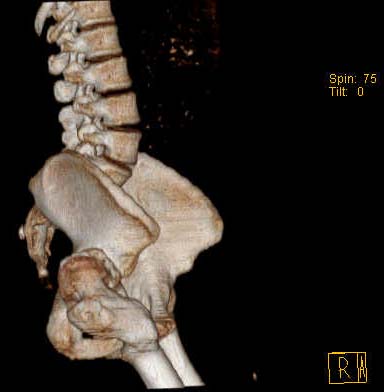

Уважаемые коллеги!Женщина, 35 летВ прошлом по поводу врожденного вывиха бедра перенесла операцию остеотомии по Шанцу

с удлинением правой ноги за счет бедра на уровне диафиза. В последнее время прогрессируют боли в правом тазобедренном суставе, порочное положение правой ноги, затруднена ходьба.Вопросы:1) Целесообразно ли эндопротезирование правого тазобедренного сустава?2) Целесообразный ли следующие действия: канал бедренной кости предполагаем вскрыть для введения ножки протеза на высоте угловой деформации, предполагаем низведение большого вертела с мышцами; протез будет подобран индивидуально, предполагается умеренная версия?В приложении рентгенограммы и трехмерная КТ.В цветном и более качественном варианте КТ размещена здесь